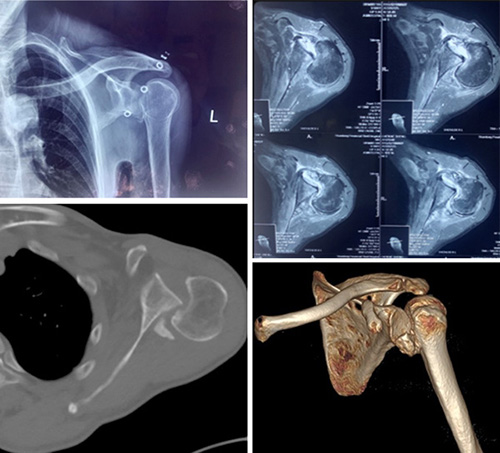

近日,山东第一医科大学附属省立医院(山东省立医院)创伤中心成功为一名陈旧性绞锁性肩关节后脱位合并肱骨头骨折(反Hill-Sachs损伤)患者进行反式肩关节置换手术。该手术的顺利实施,体现了我院处理复杂肩肘创伤病例的领先能力。

面对这例受伤时间长、脱位类型少见、骨折情况复杂的患者,创伤中心常务副主任李连欣组织全科病例讨论,通过分析认为该患者为“陈旧性绞锁性肩关节后脱位合并肱骨头骨折(反Hill-Sachs损伤)”,患者疼痛活动障碍,不能继续保守治疗,需要进行手术。患者的手术难点在于:患者为陈旧性后脱位,周围组织已经严重粘连、僵硬;脱位的肱骨头卡于关节盂造成关节面缺损,很难恢复肱骨头原本的解剖结构;合并肩袖巨大陈旧性撕裂,难以修复;患者为老年,骨质疏松明显;病程长达10年,即使手术勉强恢复其解剖关系,未来发生肱骨头缺血坏死、创伤性关节炎等并发症的几率极高。经过科室充分讨论分析,最终确定反式肩关节置换的手术方案。

肩关节脱位俗称脱臼,是临床常见损伤,后脱位少见,仅占肩关节脱位的2%, 合并肱骨近端骨折的罕见,其发病因素主要是外伤暴力及骨质疏松。一般临床上把骨折脱位时间在三周以上的称为陈旧性骨折或脱位。对于肩部脱位多数可以手法复位获得较好效果,新鲜骨折通过手术复位固定一般也可获得满意的效果,但对于陈旧性脱位或骨折,由于关节的挛缩、粘连等,骨折断端和周围存在大量瘢痕组织和骨痂,时间再长即导致畸形愈合,复位十分困难,也难以实施内固定。实施关节置换也存在软组织不平衡,脱位,神经损伤等风险,手术很有挑战性。